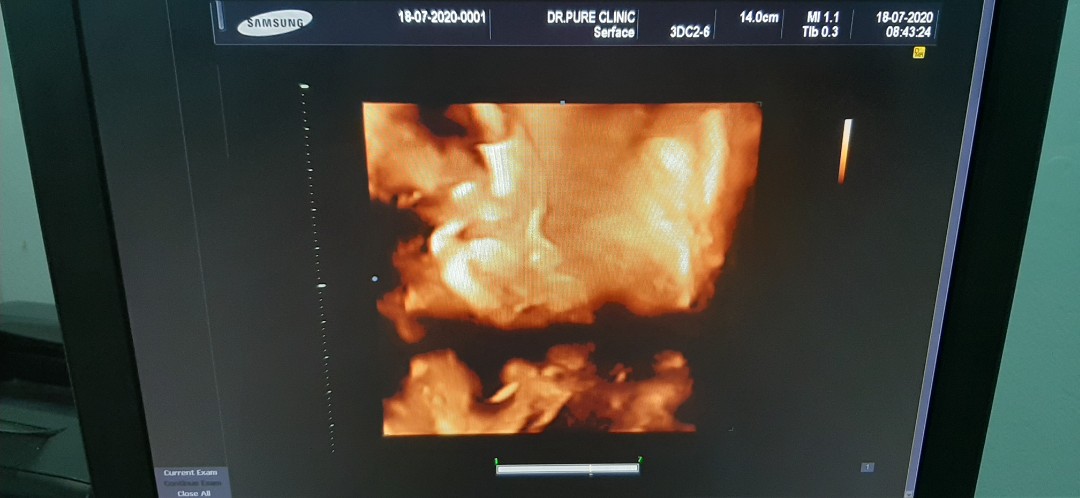

มุมเดียวกันเลยค่ะ

เห็นเท่านี้เองจ้า